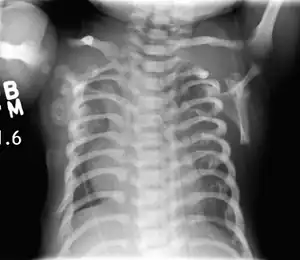

CXR of a newborn with asphyxiating thoracic dysplasia. Note the short ribs.

Asphyxiating thoracic dysplasia (ATD), also known as Jeune syndrome, is a rare inherited bone growth disorder (autosomal recessive skeletal dysplasia) [1]that primarily affects the thoracic region. It was first described in 1955 by the French pediatrician Mathis Jeune.[2] Common signs and symptoms can include a narrow chest, short ribs, shortened bones in the arms and legs, short stature, and extra fingers and toes (polydactyly). The restricted growth and expansion of the lungs caused by this disorder results in life-threatening breathing difficulties; occurring in 1 in every 100,000-130,000 live births in the United States.[3][4]

Jeune syndrome is a rare genetic disorder that affects the way a child’s cartilage and bones develop. It begins before the child is born and primarily affects the child's rib cage, pelvis, arms and legs.[6] Usually, problems with the rib cage cause the most serious health problems for children with Jeune syndrome. Their rib cages (thorax) are smaller and narrower than usual, which inhibits the child's lungs from developing fully or expanding when they inhale. The child may breathe rapidly and shallowly. They may have trouble breathing when they have an upper or lower respiratory infection, like pneumonia. Breathing trouble can range from mild to severe. In some children, it is not noticeable, aside from fast breathing; however, in others, breathing problems can be fatal. About 60% to 70% of children with this condition die from respiratory failure as babies or young children. Children with Jeune syndrome who survive often develop problems with their kidneys, and over time they may experience kidney failure.[2]